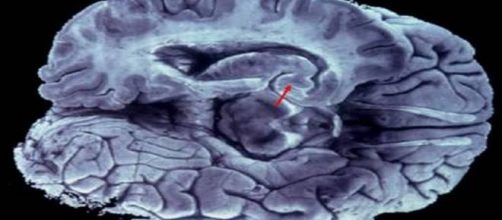

A fault in the frontal lobe and cerebral cortexmay be the cause of auditory and visual hallucinations, without the need for the use of substances. At least in Australia, such hallucinations affects on average one in every 20 people, showing flaws in their perception of reality by all the senses, although visual and hearing are the most common.

This is what was announced by the specialist of the Queensland Brain Institute, John McGrath, who explained that sometimes something goes wrong in the frontal-cortex lobe relationship, and the failure of perception or hallucination is generated, the Australian Broadcasting Corporation (ABC) .

He noted that when all goes well, the frontal lobe is the command and controls the whole brain, but situations such as these, reduce their efficiency and when you can create hallucination.He explained that when all goes well, the frontal lobe of the brain controls the whole, but in situations such as these, reduce their efficiency and when you can create hallucination.